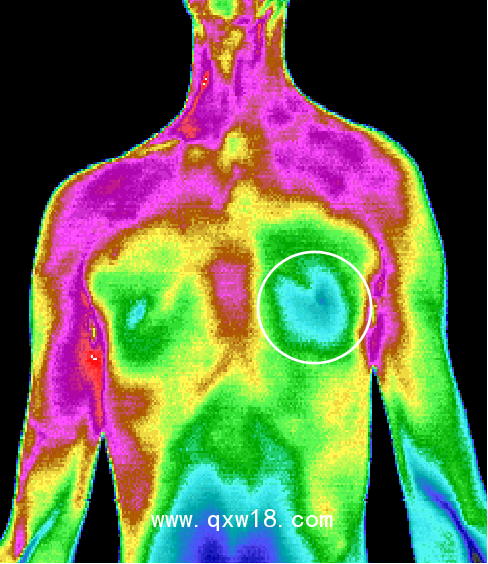

中醫(yī)熱CT是醫(yī)學(xué)技術(shù)和紅外攝像技術(shù)、計(jì)算機(jī)多媒體技術(shù)結(jié)合的產(chǎn)物,人體是一個(gè)天然的生物發(fā)熱體,由于解部結(jié)構(gòu)、組織代謝、血液循環(huán)及神經(jīng)狀態(tài)的不同,機(jī)體各部位溫度不同,形成不同的熱場(chǎng),中醫(yī)熱CT被動(dòng)接收人體組織細(xì)胞代謝熱源,可以反映出人體局部0.05°C~0.1°C的溫度微弱變化,0介入、0損傷、0輻射、0痛苦,結(jié)合Al智能分析可將傳統(tǒng)中醫(yī)通過(guò)“四診八綱”等原始手段獲取的人體信息,通過(guò)數(shù)值化和可視化的彩色圖像,形象客觀的呈現(xiàn)出來(lái)觀測(cè)臟腑的寒熱狀態(tài)、經(jīng)絡(luò)氣血流通情況、中醫(yī)藥效果的可視化觀察,針灸,推拿按摩,刮癡拔罐等治療的指導(dǎo)及效判定、參與九種體質(zhì)的評(píng)測(cè),拓展了中醫(yī)四診,增加了中醫(yī)的“第五種診斷方法”,推動(dòng)中醫(yī)現(xiàn)代化的發(fā)展,被形象的比喻成“扁鵲之眼”

???中醫(yī)熱CT檢測(cè)最重要的一個(gè)優(yōu)勢(shì)就是早期預(yù)警,X光、B超、CT等檢測(cè)技術(shù)都屬于結(jié)構(gòu)影像技術(shù),只有在疾病形成病灶之后才能發(fā)現(xiàn)疾病。而疾病在出現(xiàn)組織結(jié)構(gòu)和形態(tài)變化之前,細(xì)胞代謝就會(huì)發(fā)生異常。中醫(yī)熱CT可以反映出人體后部0.05°C~0.1C的溫度微弱變化,因此能更早地發(fā)現(xiàn)問(wèn)題。檢測(cè)所得為高清晰度彩色圖像,具有更直觀、更形象的特點(diǎn),結(jié)合AI智能分析,所得結(jié)果精準(zhǔn)度更高,成為了目前我們認(rèn)知亞健康最有力的測(cè)評(píng)技術(shù)。

紅外熱CT檢測(cè)最重要的一個(gè)優(yōu)勢(shì)就是早期預(yù)警。X光、B超、CT等檢測(cè)技術(shù)它們都屬于結(jié)構(gòu)影像技術(shù),只有在疾病形成病灶之后才能發(fā)現(xiàn)疾病。而疾病在出現(xiàn)組織結(jié)構(gòu)和形態(tài)變化之前,細(xì)胞代謝就會(huì)發(fā)生異常。醫(yī)用紅外熱CT可以反映出人體局部0.05°C ~ 0.1°C的溫度微弱變化,因此能更早地發(fā)現(xiàn)問(wèn)題。檢測(cè)所得為高清晰度彩色圖像,具有更 直觀、更形象的特點(diǎn),結(jié)合ai智能分析,所得結(jié)果精準(zhǔn)度更高,成為了目前我們認(rèn)知亞健康最有力的測(cè)評(píng)技術(shù)。紅外熱CT彌補(bǔ)了其他醫(yī)用影像設(shè)備的不足,并能很好地進(jìn)行影像互補(bǔ)。

6、適用廣泛:適用于臨床內(nèi)科、外科、婦科,兒科等所有科室。 可以對(duì)全身九大系統(tǒng)、上百種疾病有很好輔助診斷作用,特別是對(duì)心腦血管,乳腺,甲狀腺疾病 以及惡性腫瘤的早期發(fā)現(xiàn)有重大的參考價(jià)值。